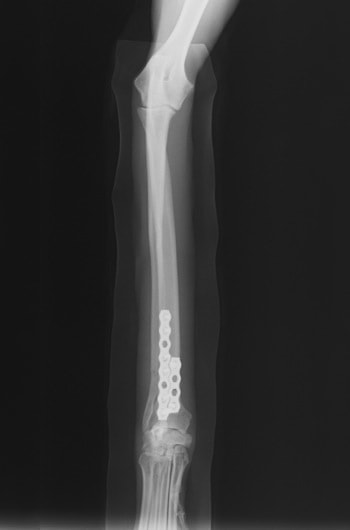

橈尺骨骨折 : 症例1 | 症例2 | 症例3 | 症例4 | 症例5 | 症例6 | 症例7

: 症例8 | 症例9 | 症例10 | 症例11 | 症例12 | 症例13 | 症例14

: 症例15 | 症例16 | 症例17 | 症例18 | 症例19 | 症例20 | 症例21

当院ではAdvanced Locking plate system(ALPS)と、Locking compression plate system(LCPS)という骨接合法で骨折症例の治療を行っています。

従来型のプレートのように広い面積で骨と接するプレートを用いて固定を行った場合、プレート下の骨はプレートとの接触面において血行が絶たれ壊死し、それがリモデリングされると骨密度が低下する。この骨密度の低下防ぐために、骨折部局所への血行を温存することの重要性が近年改めて認識されるようになってきている。Advaed Locking Plate System (ALPS)は従来型のプレートシステムの欠点を改良し、より使いやすく、より骨への血行を阻害しないようにというコンセプトで作られた。

LCPは、スクリュー(ネジ)とプレート(金属の板)をロックする特殊な構造により骨折部位を固定する新しい世代のプレートシステムです。ひとつのホールでロッキングスクリューとスタンダードスクリューの使用を選択できるユニークな構造をしているため、骨折断端間の圧迫を目的とした従来型プレート固定法に加え、高い角度安定性を有するロッキングスクリューを用いた固定法の選択が可能です。従来のプレートシステムでは困難だった部分の骨折や癒合不全の症例に高い治療効果をもたらします。